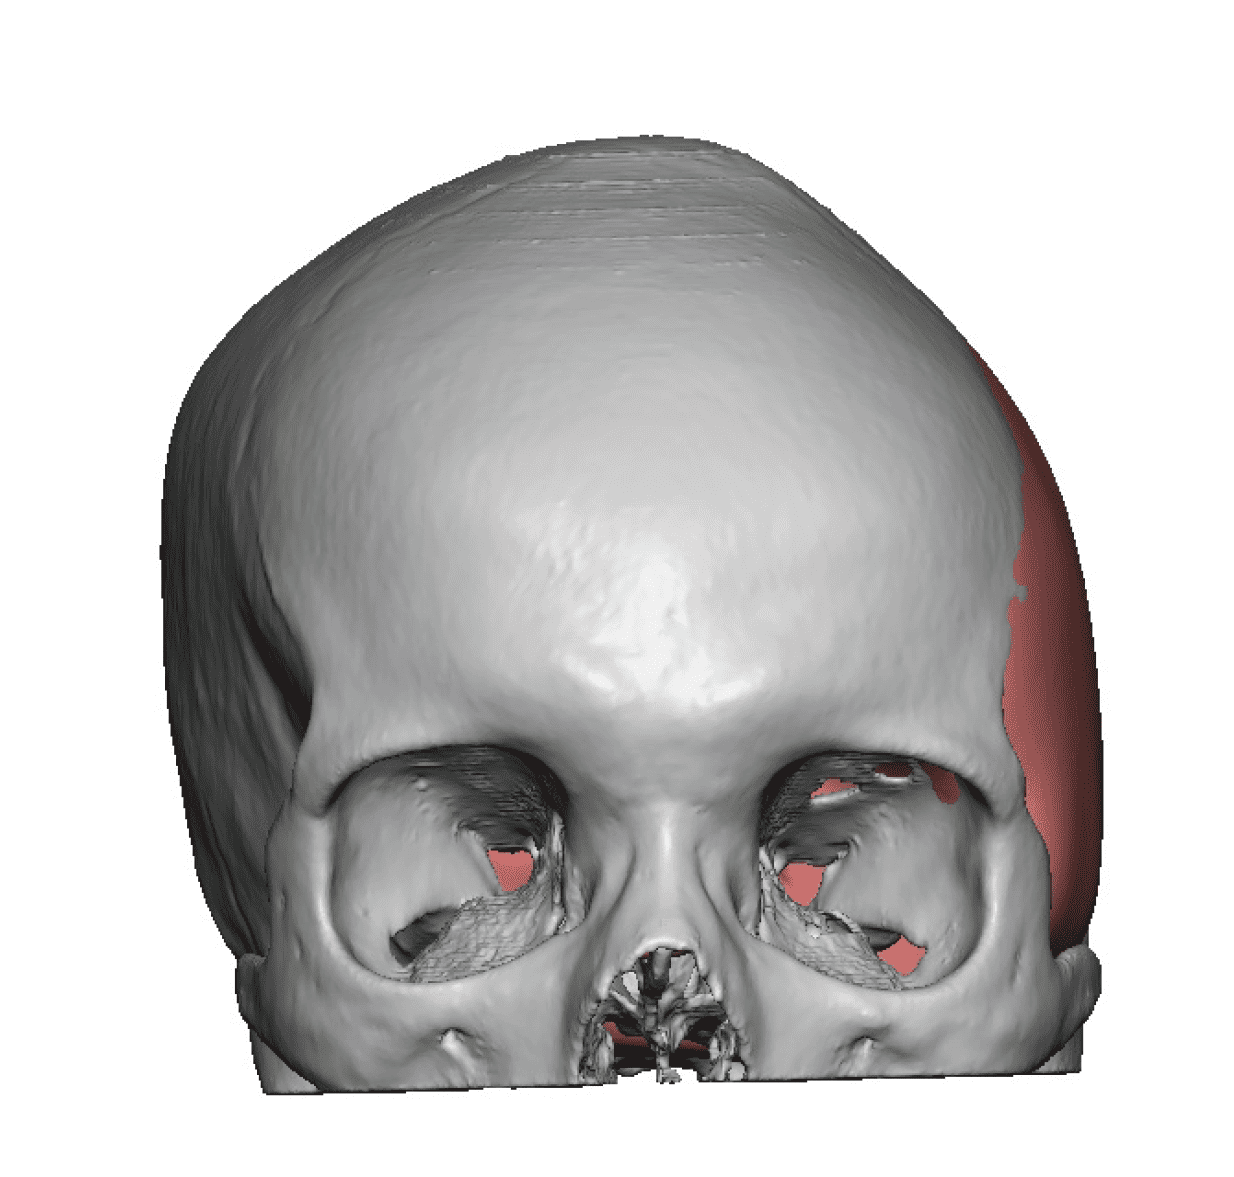

Patient 84

Desire for change of head shape from front view form an inverted V shape to a rounder and wider head shape.

Placement of custom extended forehead-temporal implants through incisions in the crease behind the ear. (he had a prior back of head skull implant which is green in the implant designs and which the head widening implants partially covered it)

Desire for change of head shape from front view form an inverted V shape to a rounder and wider head shape.

Placement of custom extended forehead-temporal implants through incisions in the crease behind the ear. (he had a prior back of head skull implant which is green in the implant designs and which the head widening implants partially covered it)